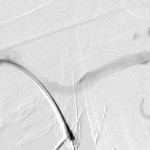

- Right brachial arteriogram during intervention: Proximal brachial artery patent.

- Reflux angiography of the access circuit was performed and revealed normal arterial limb of the circuit.